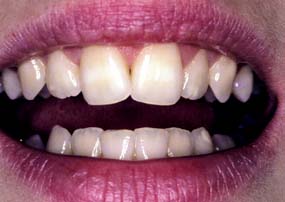

Compromised appearance is a strong motivating factor for patients to seek advice as to whether improvement is possible (Fig. 1-3). Such patients may have missing or crowded teeth, or a tooth or restoration may be fractured. Their teeth may be unattractively shaped, malpositioned, or discolored, or there may be a developmental defect.

The patient is observed for tooth visibility during normal and exaggerated smiling. This can be critical in fixed prosthodontic treatment planning,12 especially for margin placement of certain metal-ceramic crowns. Some patients show only their maxillary teeth during smiling. More than 25% do not show the gingival third of the maxillary central incisors during an exaggerated smile13 (Fig. 1-13). The extent of the smile depends on the length and mobility of the upper lip and the length of the alveolar process. When the patient laughs, the jaws open slightly and a dark space is often visible between the maxillary and mandibular teeth (Fig. 1-14). This has been called the negative space.14 Missing teeth, diastemas, and fractured or poorly restored teeth disrupt the harmony of the negative space and often require correction.15